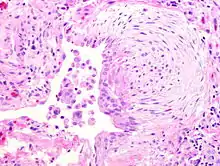

![]() | Fat necrosis | Breast lump showing an area of fat necrosis showing shadowy outlines of necrotic adipocytes surrounded by an inflammatory reaction with cholesterol clefts. | Category: Histopathology of liponecrosis | Liponecrosis |